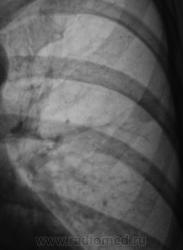

Да, было проведено стандартное дообследование. Тень, при измерении "лазерной линейкой" 6 х 7 мм. "Леинейкой" тень поймать не смогли, порекомендовали провести СКТ.

Мы заподозрили патологию по флюорограмме, проведи рентгенографию, провели линейную томографию, но тень не "поймали". И для поимки тени выбрали КТ...

КТ проведено в ОКБ. Округлое образование связано "ножкой" с костальной плеврой. Постараюсь изображения КТ выставить на следующей неделе - диск на руках у пациентки.

"Эдакий злой пушистик (и тоже за ребром)"

Да, по "прямой рентгенограмме" о пушистом и "злом" подумать можно.

Но, вот томограммы, несмотря на контуры, на зло не вдохновили.

Но, вот ребро, внушает некоторую неуверенность.